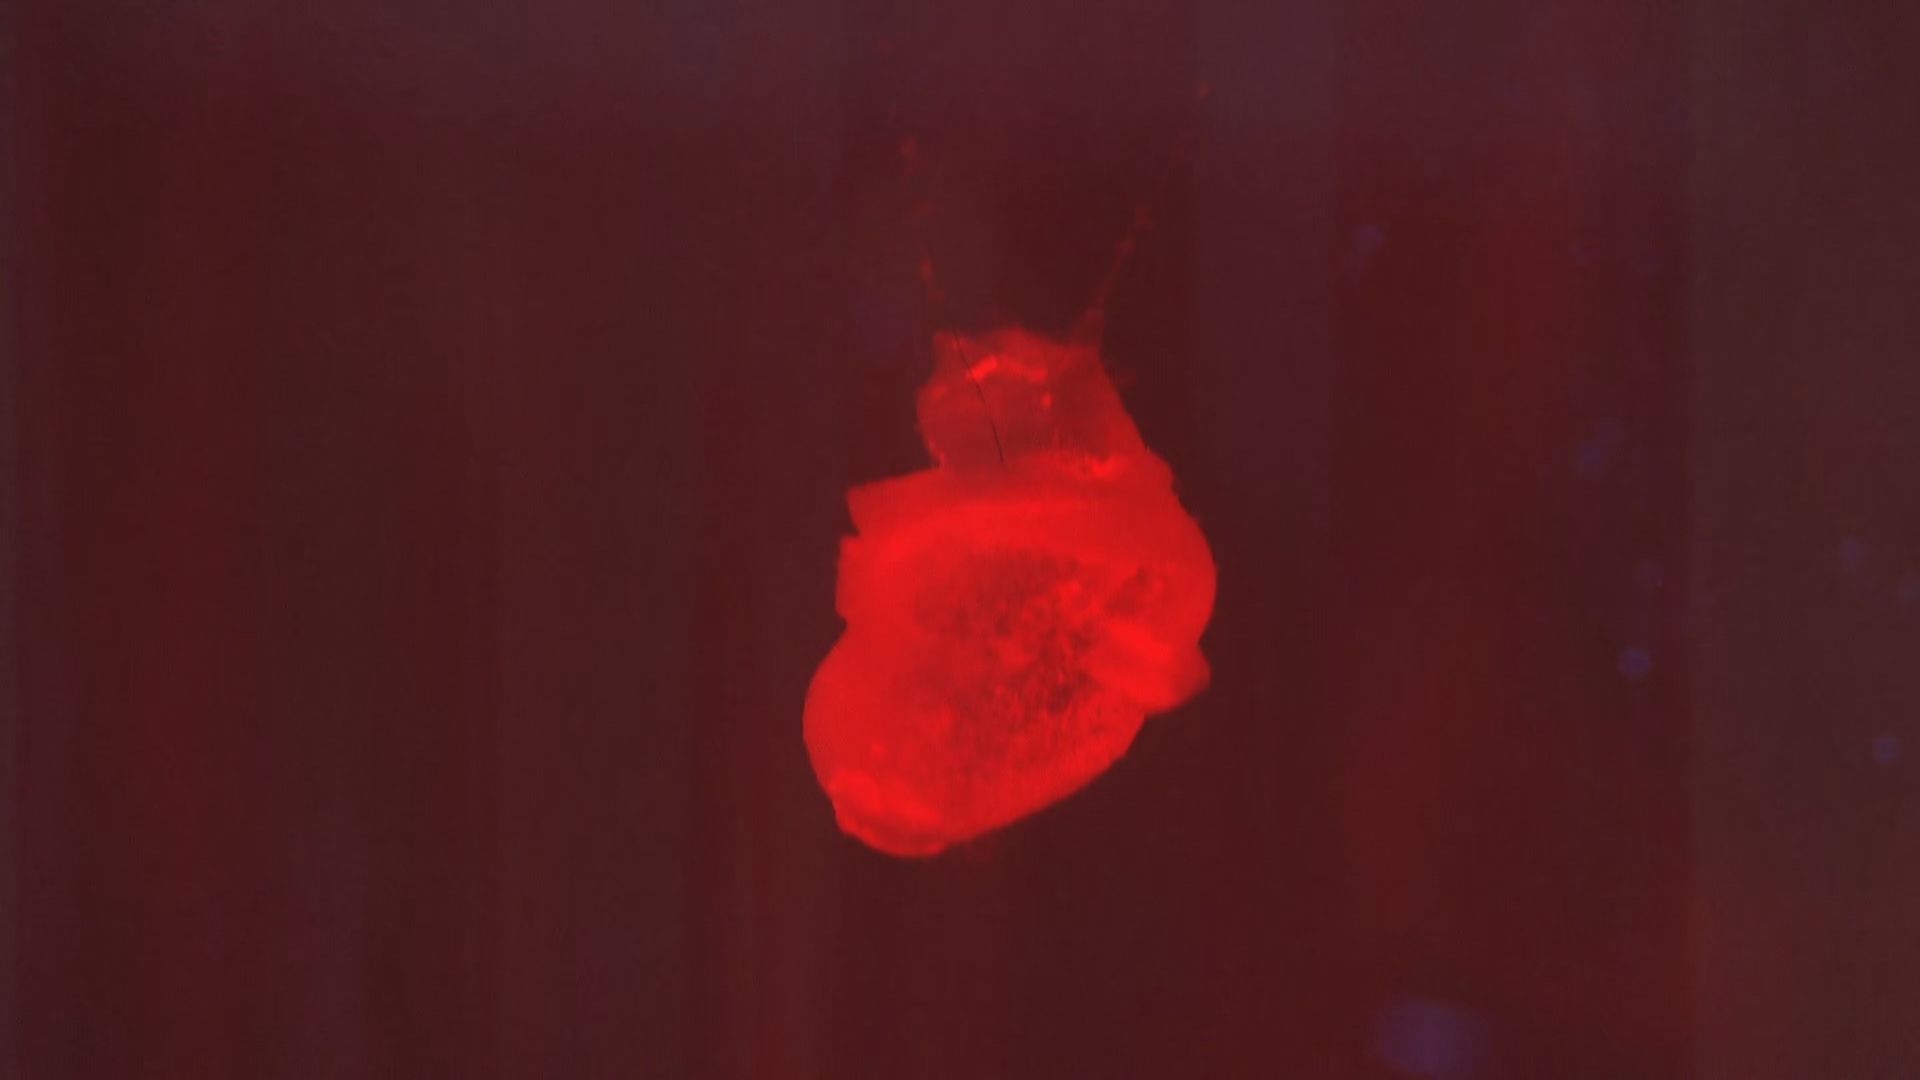

「ドク、ドク、ドク」

赤い液体の中で拍動する、親指ほどの心臓。

訪れた人がスマホ片手に展示を取り囲む。

「ほんまに動いてる。すげぇ」

「未来や、これは未来やね」

そんな声が聞こえてくる。

■万博の目玉「iPS心臓」に挑んだ医師と科学者

大阪・関西万博の目玉の一つ「iPS心臓」モデル。

展示されているパソナパビリオンには、開幕からおよそ3カ月で100万人以上が訪れた。

この心筋シートの技術を応用し、作成されたのが万博の「iPS心臓モデル」だ。

■開幕直前まで続いた微調整 完成した「iPS心臓モデル」

ちょうどいい硬さで、実際の心臓のように動くモデルを目指した結果、最終的にたどり着いたのが、厚さ0.1ミリ、3.5センチの大きさだった。

作成されたiPS心臓の内部は空洞で、弁や心室はないため、実際の心臓と同じく血液を循環させることはできない。

けれども、iPS細胞から作られた心筋細胞およそ1~2億個が、培養液の温度が人の体温に到達すると自発的に動き、実際の心臓のようにドクドクと拍動する。